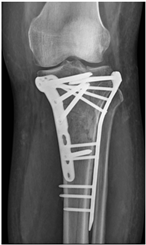

Patient C was a 42-year-old female with a left tibial fracture and underwent ORIF in February 2019. There were no known comorbidities for her. Four months after ORIF, she developed increasing tenderness, a local skin rash, a nonhealing wound, and intermittent clear discharge on the left leg. Physical examination revealed bullae formation, scaling with an erythematous base within a well-defined margin. Range of motion, distal motor function, circulation, and sensory function were intact. Radiographs confirmed a union of the tibia at the fracture site. There was no purulent drainage or fever, and the white blood cell count was 11,900/μL, which was not sufficient to confirm infection in the absence of purulence or systemic signs. She underwent a patch test for hypersensitivity, and the result showed an allergy to metal complexes. Under the impression of suspected hypersensitivity to the implants, she underwent the removal of the implants. The allergic symptoms were resolved after the implant removal. Follow-up at two months and one year showed improvement in symptoms (Figure 2).